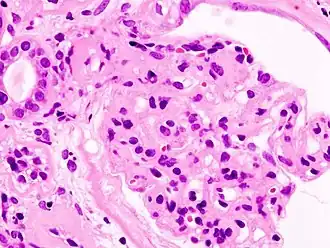

L'ultrafiltration du sang qui va donner l'urine primitive se fait dans le glomérule. Par un mécanisme physique (pression hydrostatique, pression oncotique) et biologique (sélectivité de la membrane glomérulaire aux composants sanguins), le plasma est filtré à travers la membrane basale glomérulaire (MBG) et les prolongements podocytaires qui la tapissent pour former l'urine primitive, laquelle sera ensuite successivement modifiée par les différentes structures rénales pour donner l'urine définitive. Le syndrome néphrotique est dû à une anomalie anatomique ou fonctionnelle de la membrane basale glomérulaire, qui est normalement imperméable aux protéines au-dessus d'un poids moléculaire de 60 kDa (60 000 daltons). La perte de cette sélectivité entraîne le passage de protéines dans les urines (qui apparaît lorsque les capacités physiologiques de réabsorption tubulaire des protéines sont dépassées), et donc la protéinurie et l'hypoprotidémie (malgré une synthèse accrue de protéines par le foie).

- Glomérulonéphrite extramembraneuse : par dépôt d'immunoglobulines G et de fractions du complément sérique à la face externe de la membrane basale glomérulaire.